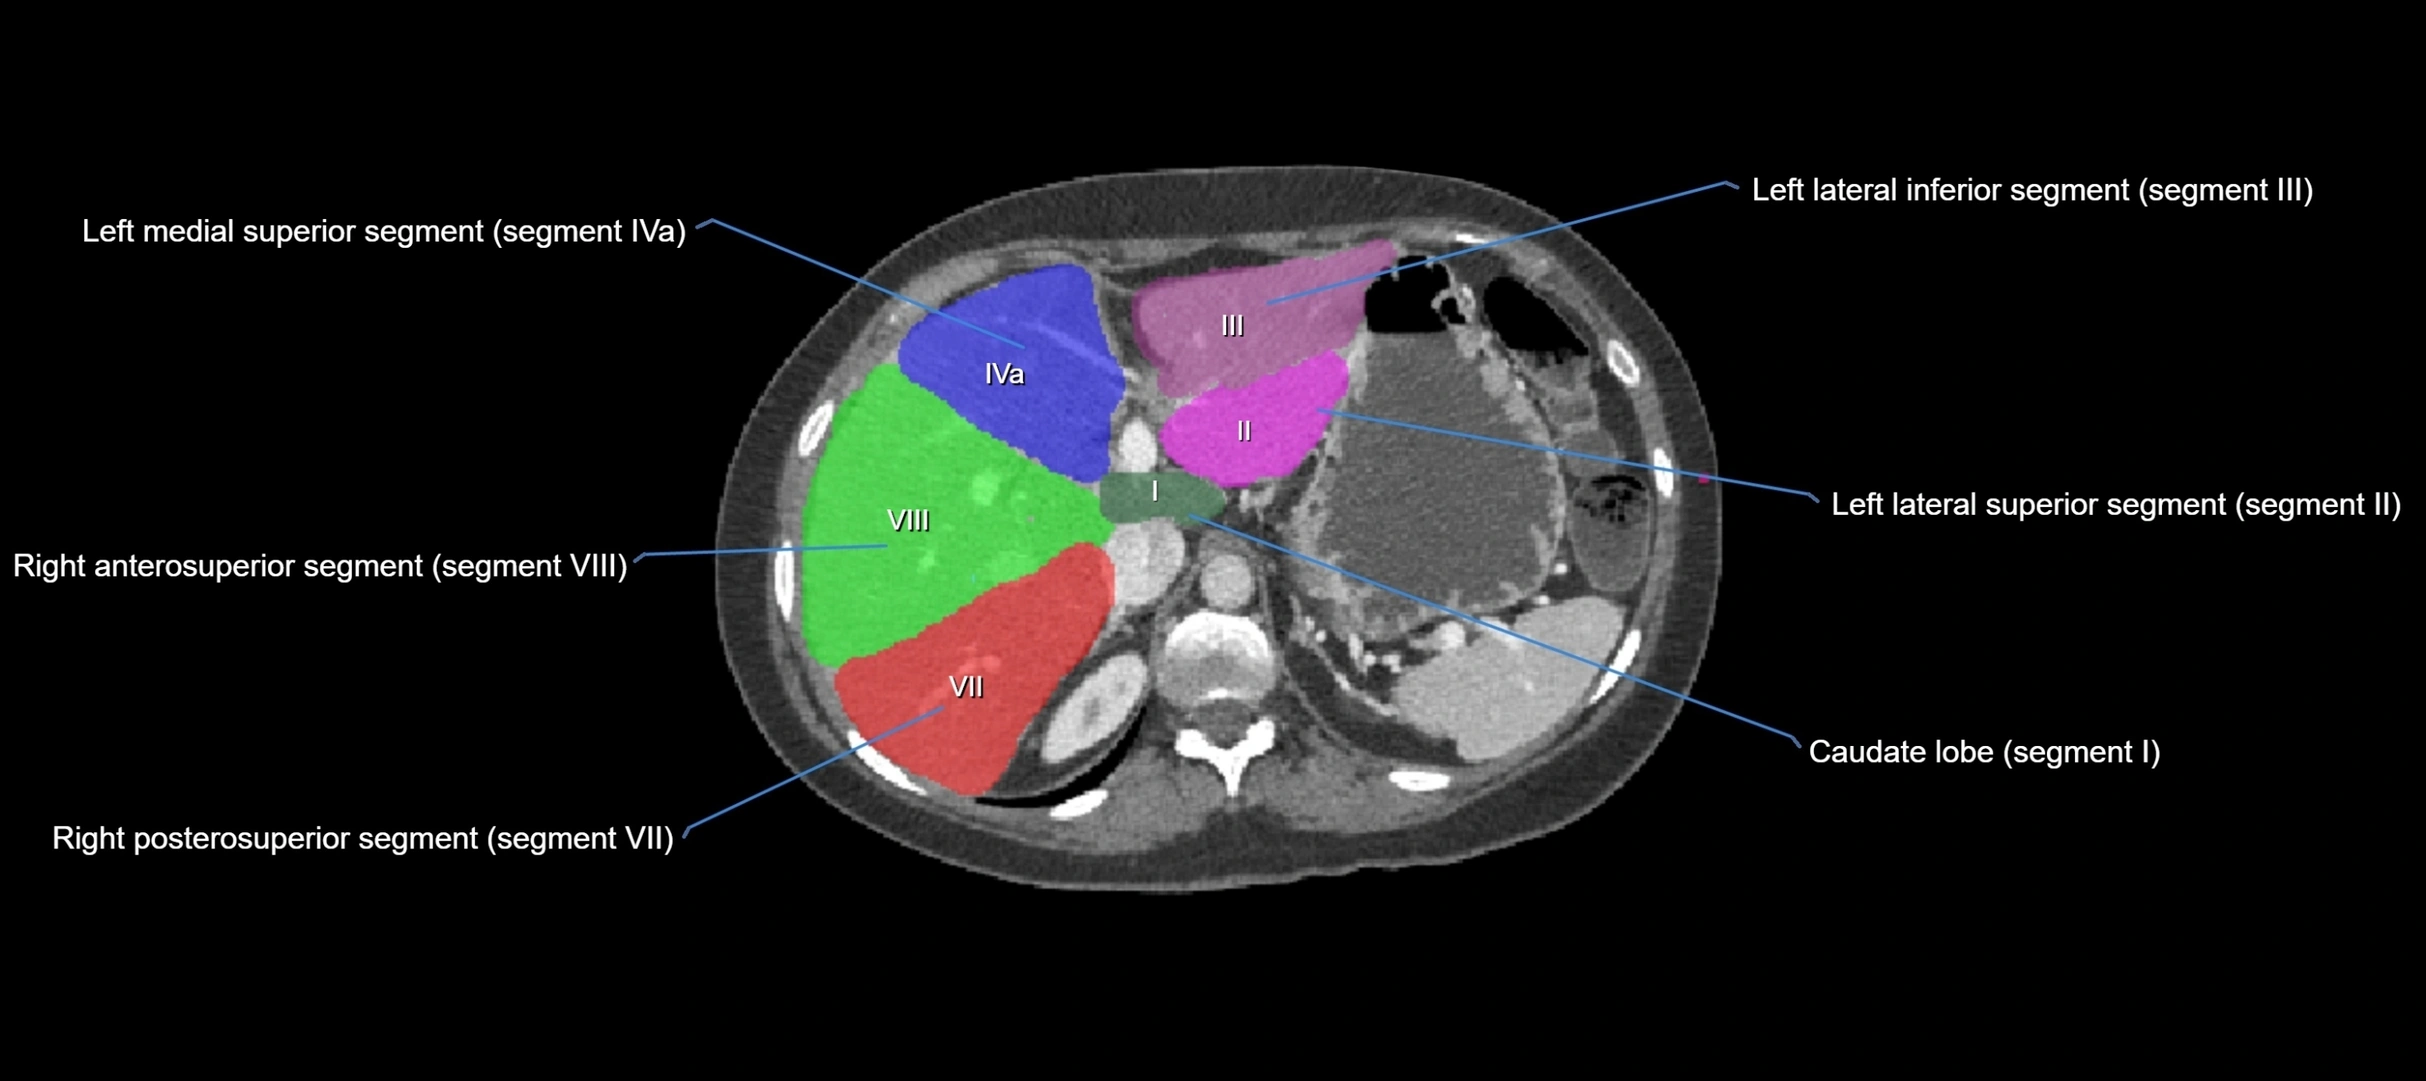

The caudate lobe of the liver is a distinct anatomical subdivision of the liver, designated as segment I in Couinaud’s classification. It lies on the posterior surface of the liver, between the fissure for the ligamentum venosum (left boundary) and the groove for the inferior vena cava (IVC) (right boundary). Superiorly, it is related to the posterior liver surface, and inferiorly it is separated from the left lobe by the porta hepatis.

The caudate lobe is unique because it receives dual portal venous and arterial inflow from both the right and left portal veins and hepatic arteries. It also has independent venous drainage directly into the IVC via multiple small hepatic veins, unlike other lobes that drain through the three main hepatic veins.

CT Image

image